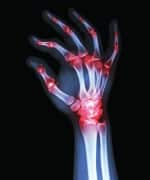

Gout is a kind of arthritis that can cause an attack of sudden burning pain, stiffness, and swelling in a joint. This often occurs in the big toe. Gout attacks can happen over and over unless properly treated. Over time, this disorder causes harm to joints, tendons, and other tissues.

Gout is caused by high concentrations of uric acid in the body.1 This condition leads to the creation of crystals in joints and tissues. Aside from pain so excruciating that some of the 8.3 million US sufferers2 often cringe at the thought of putting a sheet over their foot at night, gout is associated with higher risks of cardiovascular disease and mortality.3,4

Gout is best known for causing unbearable pain focused in the big toe. However, gout can attack multiple joints at the same time. A survey showed that attacks also occur in the ankle or foot (50% of cases), the knee (32%), a finger (25%), an elbow ( 10%), or a wrist (10%).14